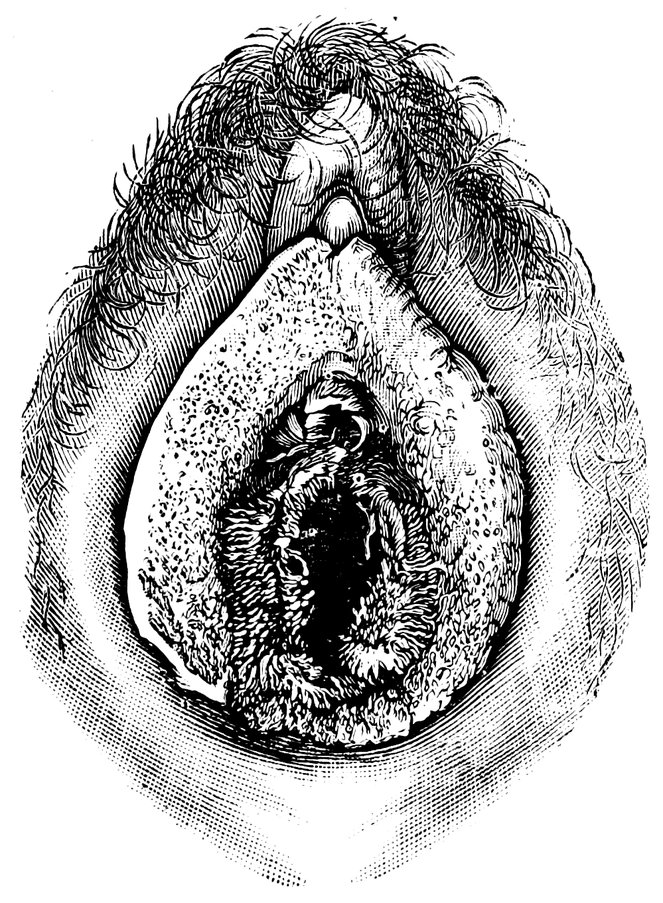

| 44. | Carunculæ Myrtiformes in a Primipara | 71 |

| 45. | Vaginal Inlet of a Multipara, without Carunculæ Myrtiformes. Slight Prolapse of Anterior and Posterior Vaginal Walls | 71 |

| 48. | The female pudendum, or vulva, with the labia majora | 204 |

| 49. | Vestibule of the vagina, with the labia minora or nymphæ, etc | 205 |